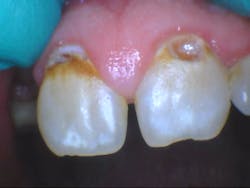

A healthy 31-year-old male reports that besides a visit to the dentist four years ago to have a bridge done on the upper right side, any previous dental visits occurred when he was around 14–15 years old. Upon initial examination with radiographs (by a previous dentist shortly after the accident), it was determined that the patient had caries on teeth nos. 8, 9, 12, 13, 15, and 30 with advanced, generalized class III periodontal disease. Interestingly enough, it was also determined that the patient was “totally temporarily disabled” for one week following his surgery and extractions. One week.

- Additional caries were noted on nos. 10, 11, 14, 26, 27, and 29—primarily facial/buccal caries (figures 3–8)